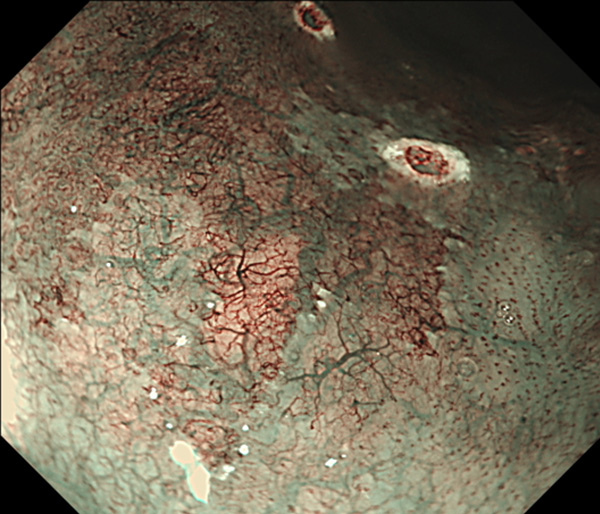

内視鏡所見と病理組織像の1対1対応が可能な症例を公募いたします。主にLSBEに発生した早期癌(HGDを含む)を対象としますが、興味深い症例であればSSBE癌でも結構です。採否は世話人へご一任ください。

症例呈示希望者は応募用紙に記入の上、代表的な内視鏡(2枚)、切除標本(新鮮、固定)、切り出し図、マッピング、代表的組織像とともに、Barrett 食道研究会事務局 barrett.shinshu@gmail.comへお申し込み下さい(10MB以下でお願い致します)。

特に、本邦では極めて稀なlong segment Barrett’s esophagus(LSBE)から発生した早期癌は、診断に難渋する場合も多く、欧米ではランダム生検による検出が標準的とされています。背景のBarrett食道もろとも全体を内視鏡切除+ラジオ波焼灼する欧米と異なり、ESDで内視鏡的な局所切除が基本の本邦では、存在診断+範囲診断(特に水平)を的確に行うことが不可欠です。

そのためには、一流の病理医による組織学的診断とエキスパート内視鏡医による拡大内視鏡像との一対一対応を徹底的に行うことで、『本来、見えないであろう拡大所見の先にある組織構築像が診えてくる』所まで内視鏡診断レベルを上げていく必要があります。その実現には、一対一対応を追究した症例(特にLSBE発生例)1例でも多く経験するしかありません。本研究会でBarrett食道腺癌(LSBE発生早期病変)を共に学び、拡大内視鏡像の一歩先を診るスキルを習得しましょう!一人でも多くの皆様のご参加をお待ちしています。